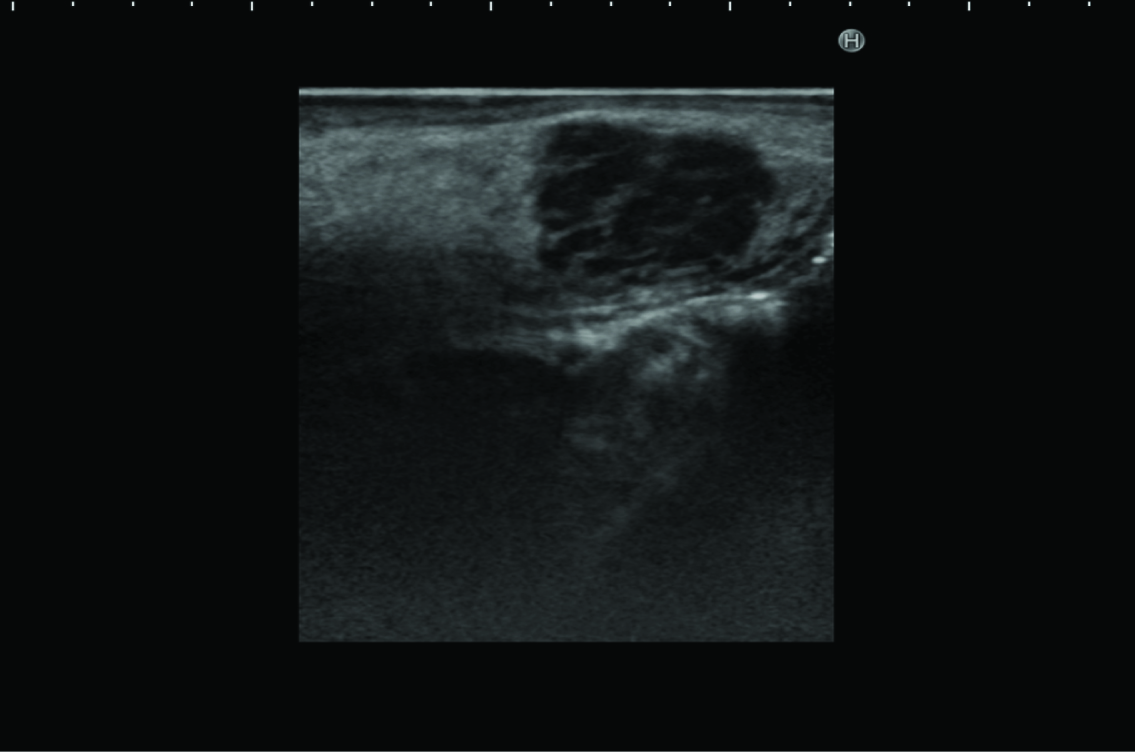

Ultrasonography revealed a rounded mass in the right side of the tongue, with irregular, unsharp borders. Ultrasonography demonstrated a predominantly hypoechoic appearance, with some hyperechoic foci [Table/Fig-2]. Magnetic resonance imaging (MRI) demonstrated a mass in the right side of the tongue, with slightly elevated signal intensity on T2-weighted imaging, and weak enhancement on gadolinium-enhanced T1-weighted imaging [Table/Fig-3a,b]. Laboratory analyses showed: white cell count, 3,000/μl; lactate dehydrogenase, 188 U/l; serum alpha-fetoprotein (AFP), 182 ng/ml; serum IgG, 480 mg/dl; serum IgM, 571 mg/dl; and serum IgA, 4 mg/dl. The tumour was initially diagnosed clinically as salivary gland tumour, such as pleomorphic adenoma. However, we considered that the tumour might represent malignant lymphoma, because the patient had already been diagnosed with AT.

Ultrasonography reveals a rounded mass in the right side of the tongue, with irregular, unsharp borders. The sonogram demonstrates a predominantly hypoechoic appearance, with some hyperechoic foci